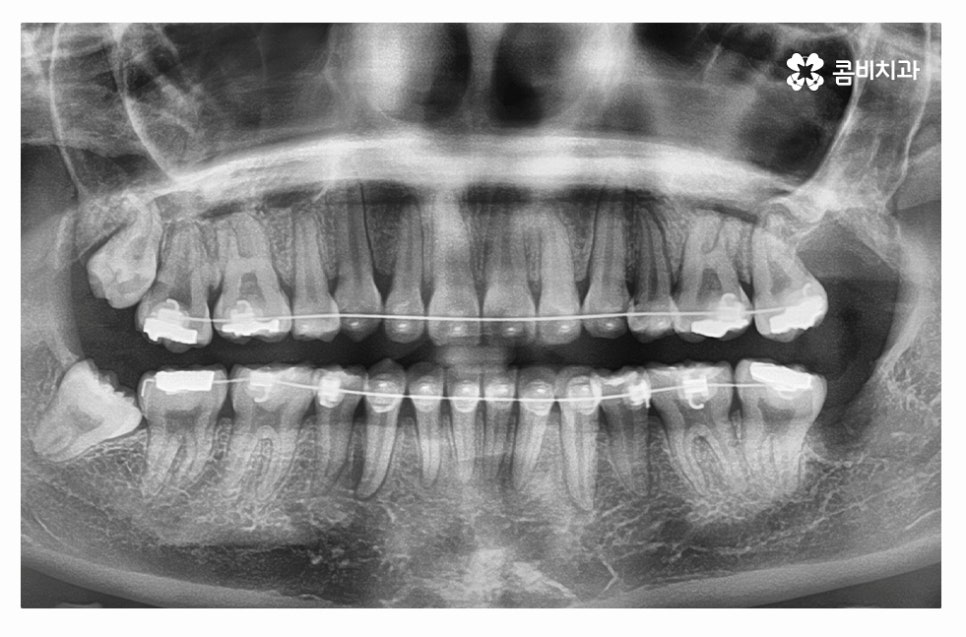

누운사랑니발치의 경우 일반적인 사랑니 발치보다 치료 난이도가

높은 편이기 때문에 고난도 발치에 해당하는 경우

대학병원에 가야 하는 경우도 있지만 우선해야 할 점이라면

사랑니를 3D CT를 활용하여 정확하게 검진해야 하고

누운 사랑니 발치에 대한 이해도가 높고 경험이 풍부한 의사를

찾는 것이 좋으며 해당 진료와 관련된 전문의 자격증이 있는

의료진을 찾는 것도 좋은 방법이라고 할 수 있어요.